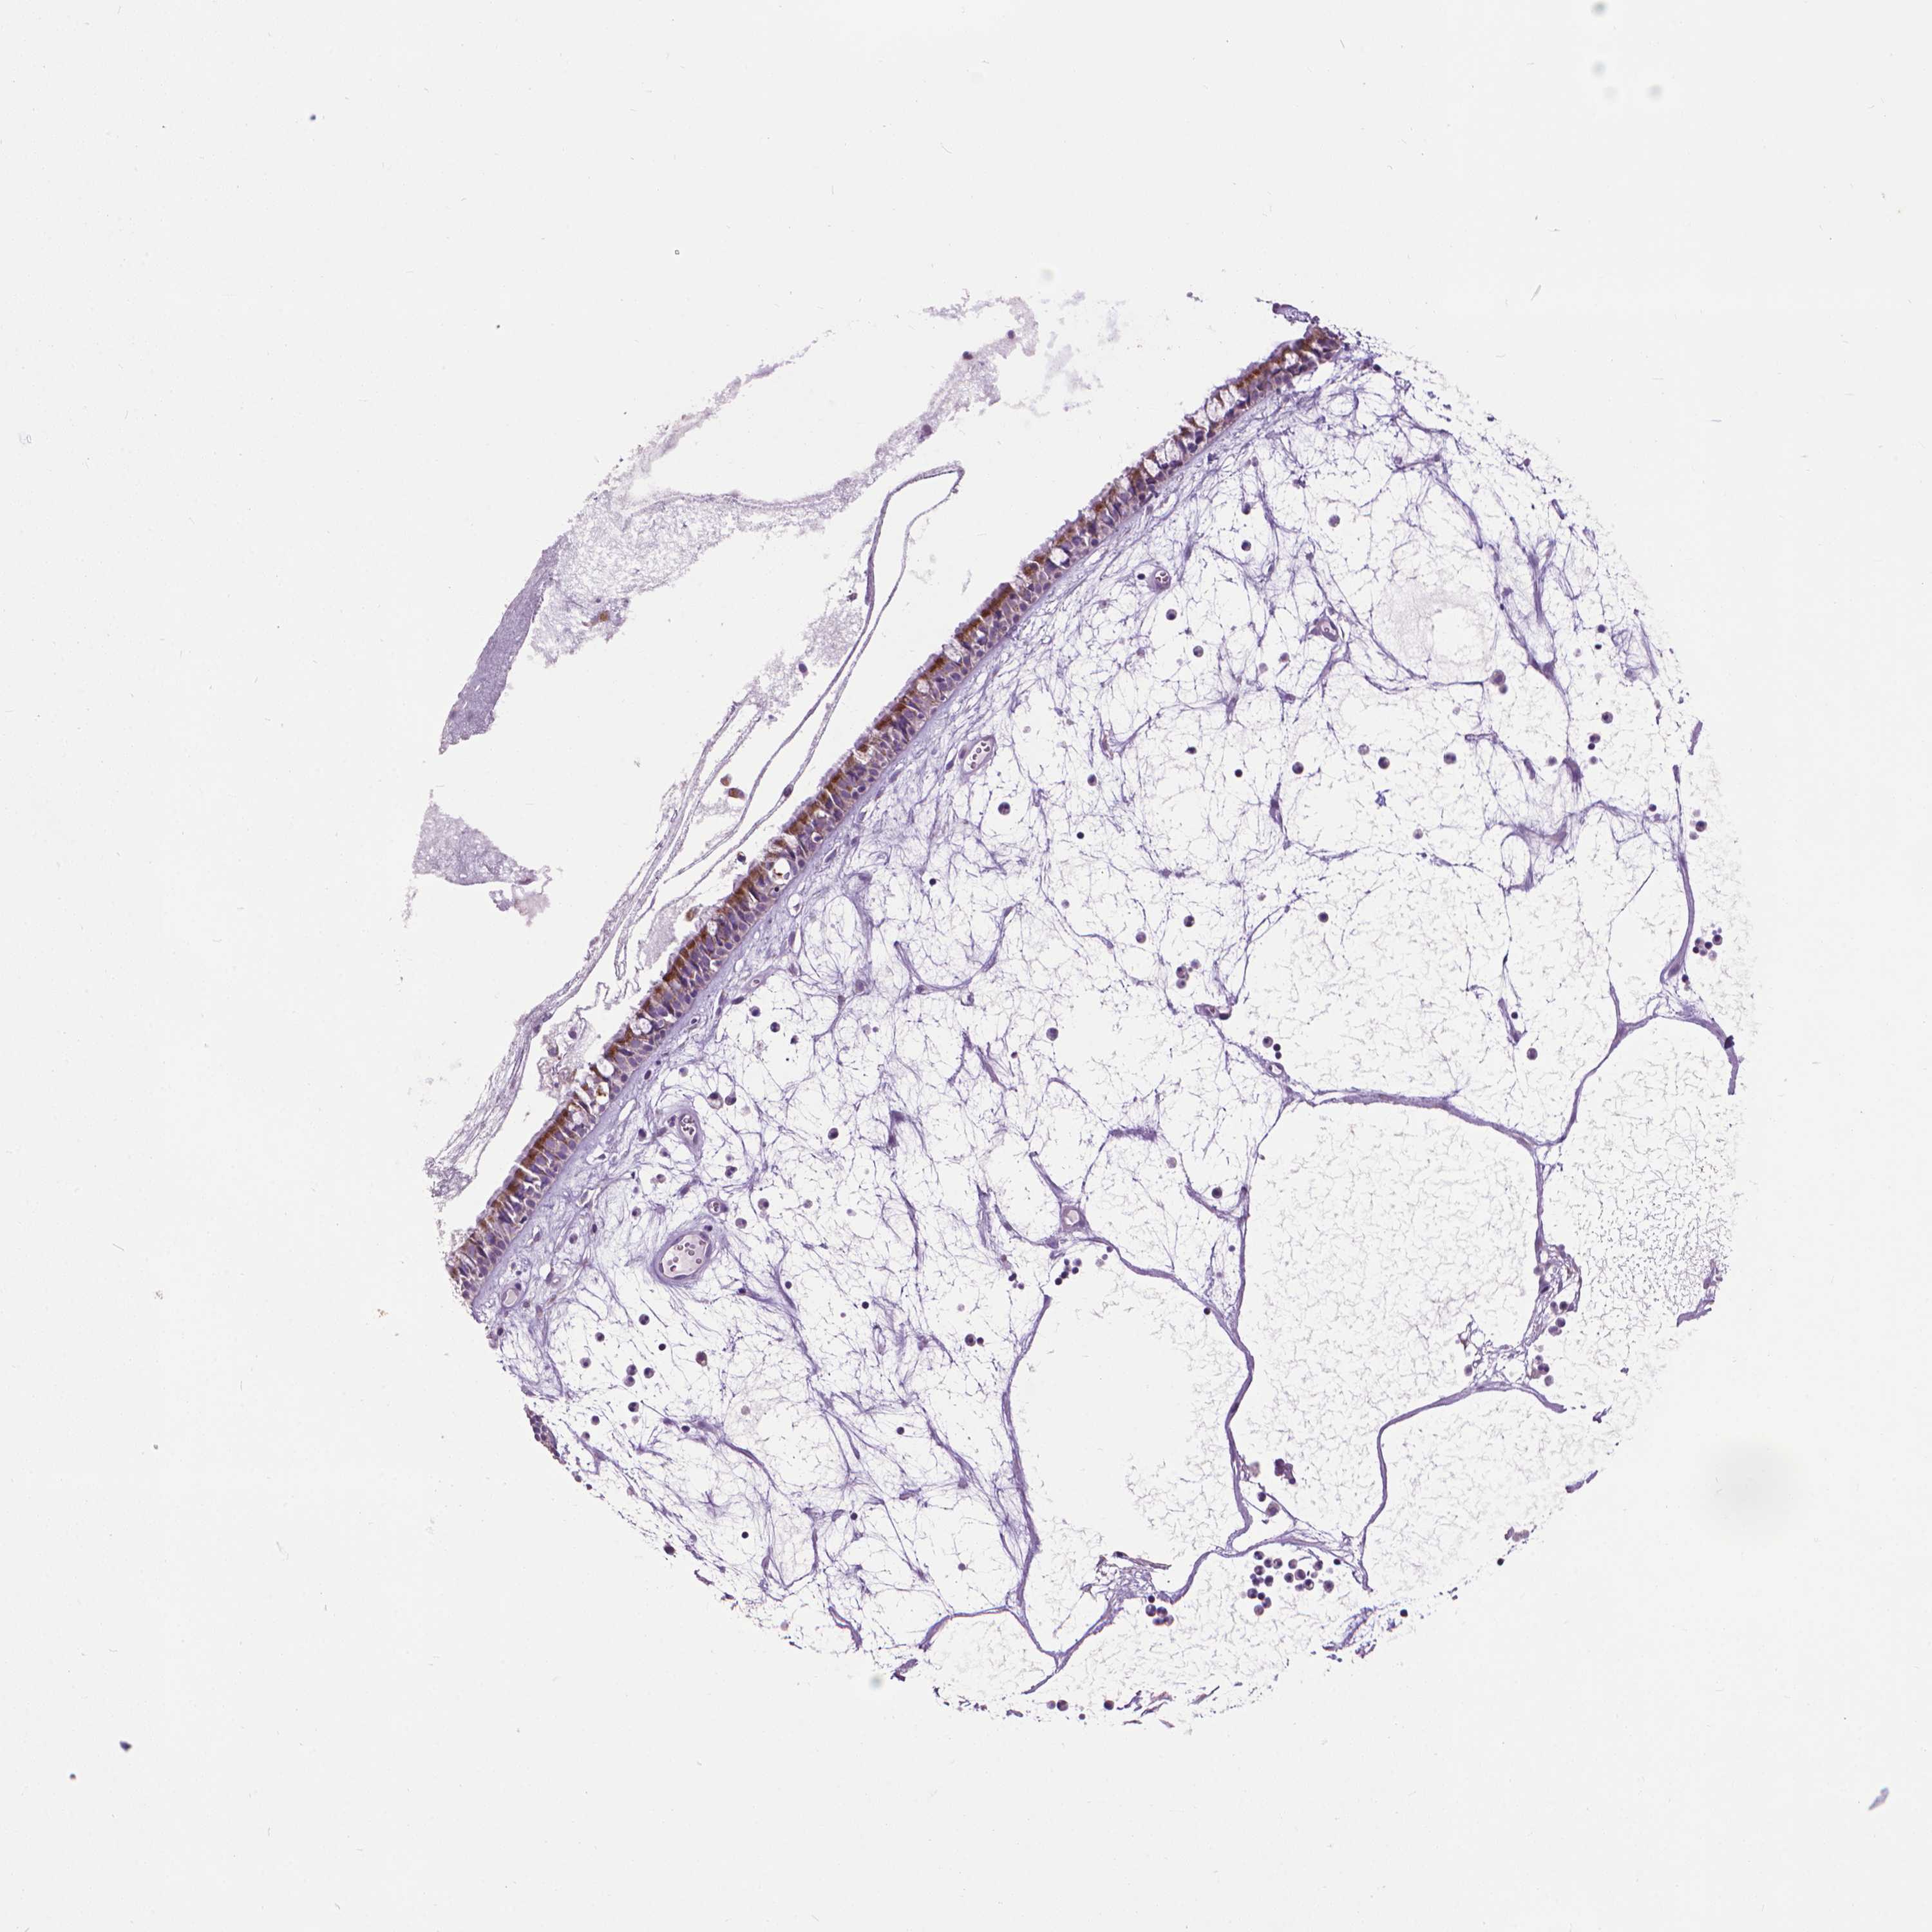

NASOPHARYNX - Antibody stainingi

Antibody staining in the annotated cell types in the current human tissue is reported as not detected, low, medium, or high, based on conventional immunohistochemistry profiling in selected tissues. This score is based on the combination of the staining intensity and fraction of stained cells.

Each image is clickable and will lead to virtual microscopy that enables deeper exploration of all samples and also displays staining intensity scores, fraction scores and subcellular localization as well as patient and tissue information for each sample.

Antibody HPA030780Antibody CAB005885Antibody CAB072343

Respiratory epithelial cells HighHighHigh